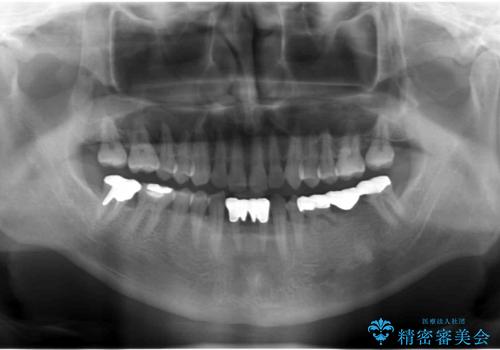

奥歯のインプラント 大人になって残っていた乳歯がダメになった

- 奥歯のブリッジの違和感を主訴に来院。

乳歯を使ってブリッジにしていましたが、支台歯が両方虫歯になっており、根が短くなって持たなくなった乳歯を抜いて、インプラントにすることになりました。

- 105.6万円(インプラント 20万円x2、カスタムアバットメント10万円x2、ジルコニアクラウン10万円x3、仮歯2万円x3)費用は治療当時の料金となります